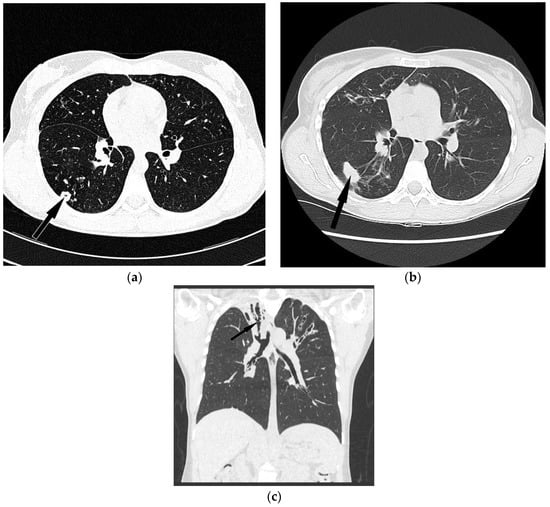

4.3. Radiological Data